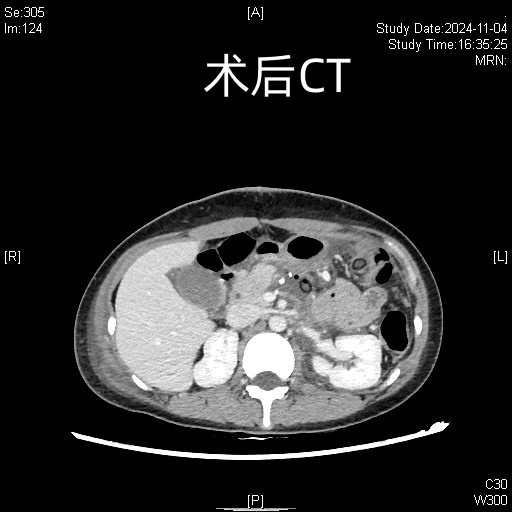

田毅峰教授、陈实教授经过数字成像智能评估后,准确分析并制定出微创下切除肿瘤的最便捷路径,为赵某实施机器人辅助胰体尾脾切除术,术中借助机器人高清的三维视野、灵活的机械臂、精细操作,在狭小的空间中最终完整切除肿瘤,成功实现微创手术,术后恢复良好,患者腹部只留下4cm的隐匿伤口,做到“大切除、小伤口”,充分体现了机器人智能系统在胰腺外科中的极致优势。

术前术后对比图